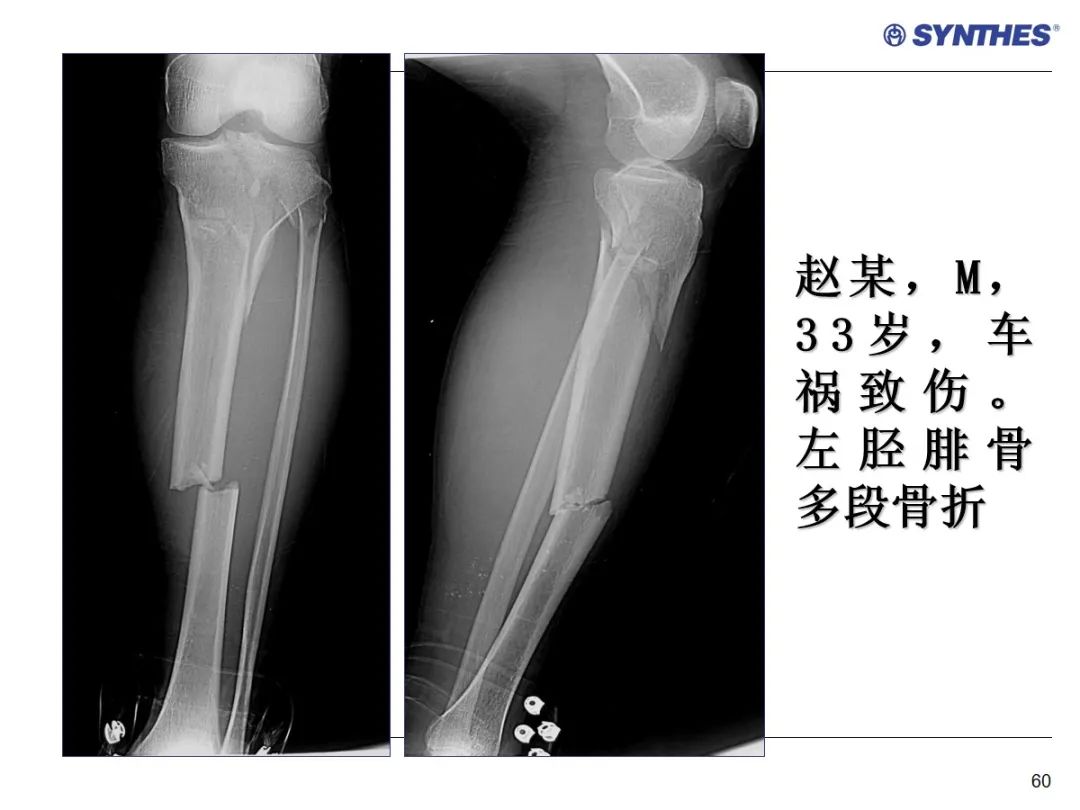

LISS微创固定系统应用技巧,原来如此简单!